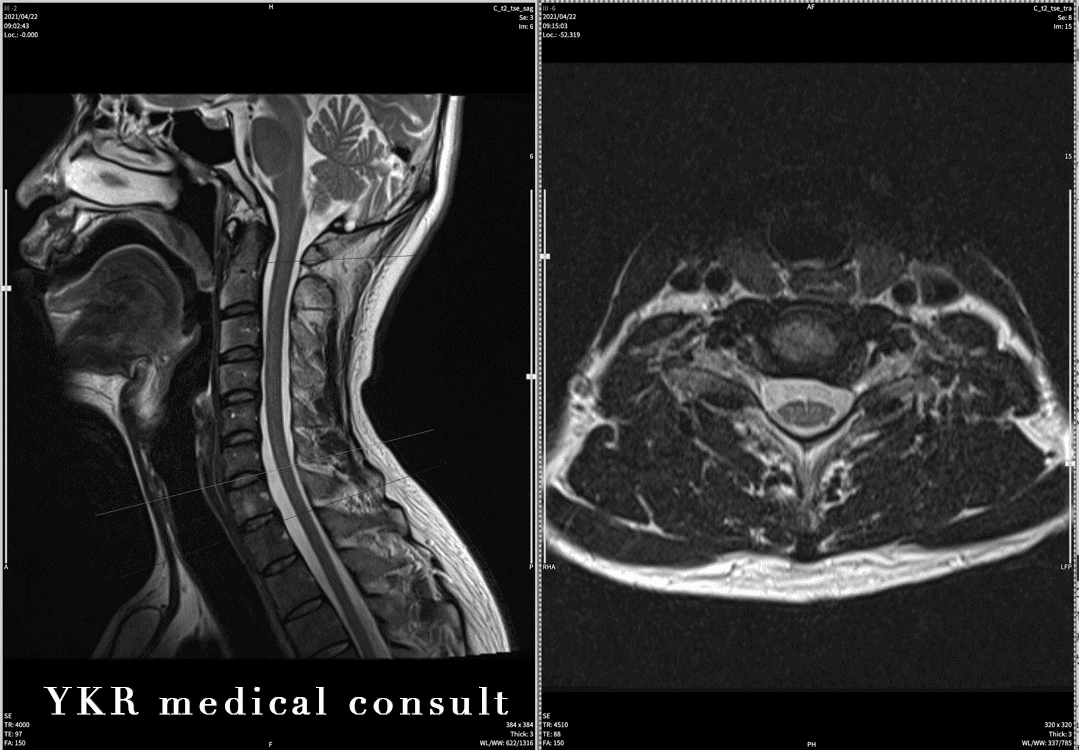

『交通事故意見書(非骨傷性頸髄損傷)⇒非該当から14級認定へ』依頼内容content明らかな画像所見のない場合でも、被害者の症状経緯から後遺障害を認めた事例(中心性頸髄損傷)本件事故は、停車中の被害者車両に、後方から制限 […]